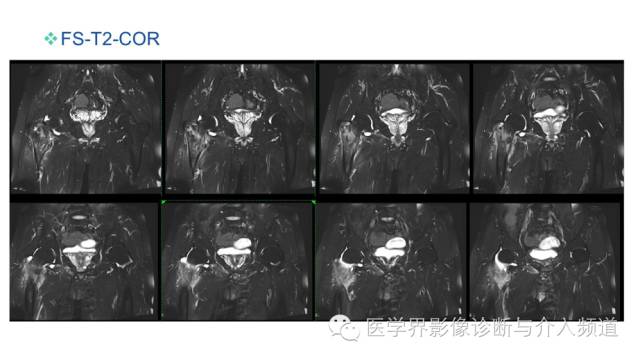

• 椎管内硬膜外脂肪增多症与终丝脂肪沉积

椎管内硬膜外脂肪增多症与终丝脂肪沉积

• 常见易忽略的疾病—椎管内硬膜外脂肪增多症

常见易忽略的疾病—椎管内硬膜外脂肪增多症

• 椎管内硬膜外脂肪增多症

椎管内硬膜外脂肪增多症